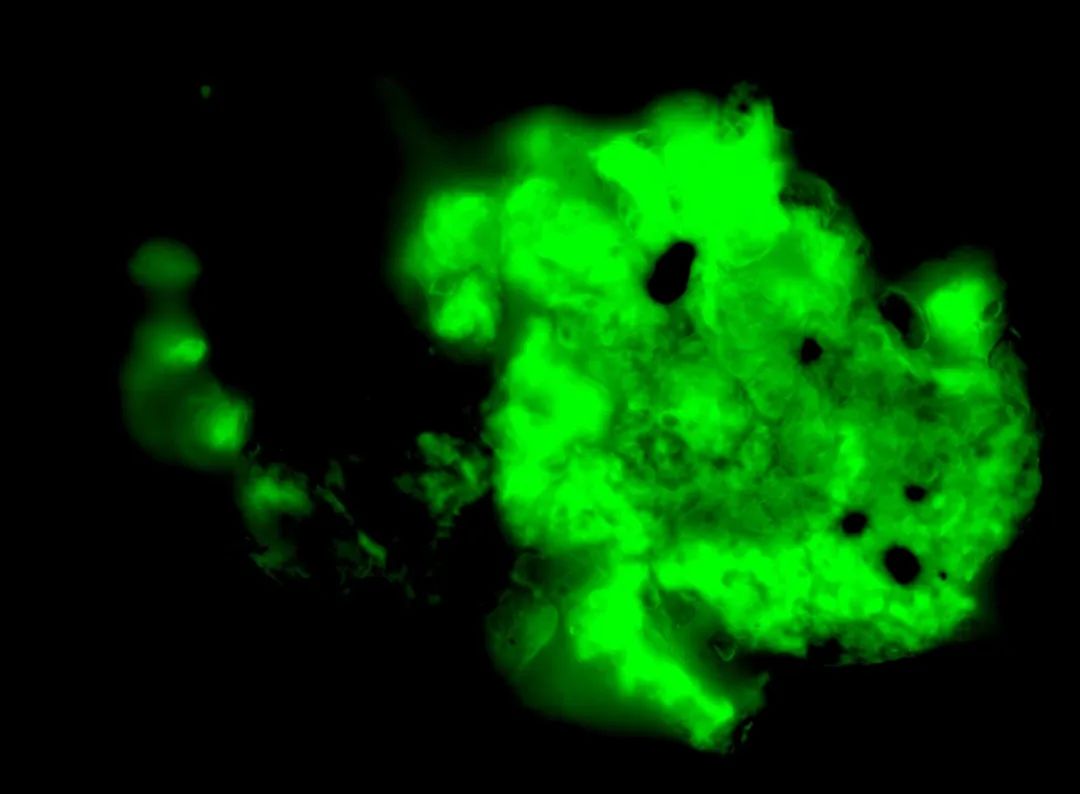

荧光显微镜图像显示、长期 COVID 患者血液中的严重微血块。COVID 凝块更能抵抗称为纤维蛋白溶解的自然凝块破坏过程,并且不易分解。CHANTELLE VENTER 和 RESIA PRETORIUS 的显微照片

“我们在糖尿病和其他疾病中发现的微血块之间的主要区别在于它们很容易分解,”Pretorius 说。COVID 微凝块更难分解。

被困在持续存在的微凝块内,她的团队发现了高水平的炎症分子和一种叫做 alpha 2-antiplasmin 的蛋白质,可以防止它们分解。

他们还发现,在存在尖峰的情况下,微凝块对纤维蛋白溶解的抵抗力更强——纤维蛋白溶解是一种能够去除凝块的自然过程。